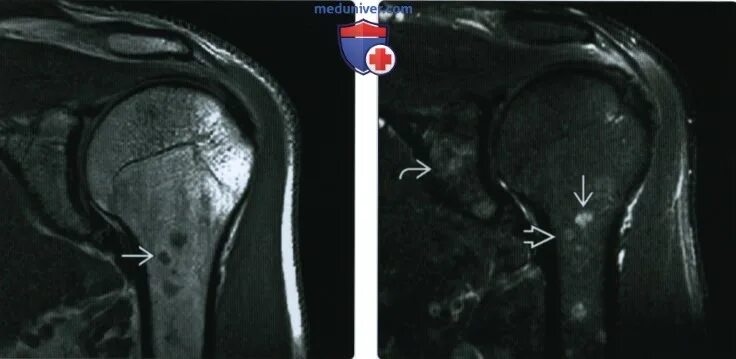

Метастазы костей мрт